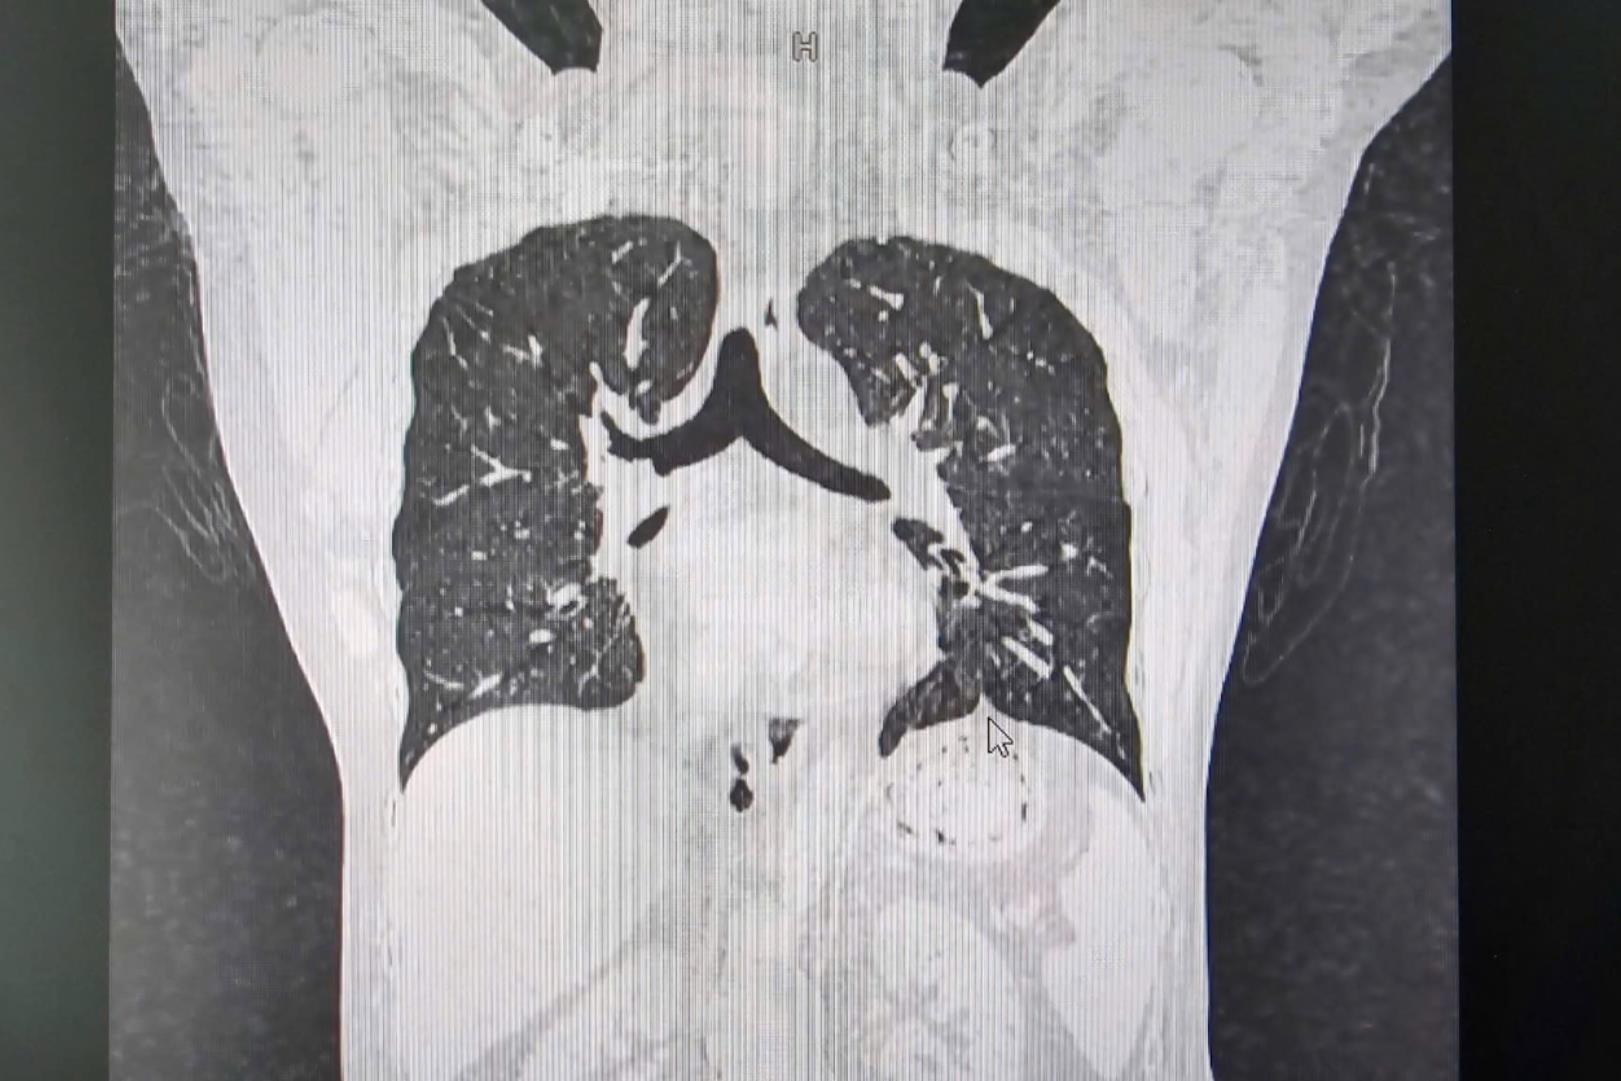

Hình ảnh chụp cắt lớp điện toán đa lát cắt. Ảnh: BVCC

Kết quả chụp cắt lớp điện toán đa lát cắt (MSCT) cho thấy tình trạng giảm thể tích phổi hai bên (thiểu sản phổi); thiểu sản nhóm cơ thắt lưng, cơ thẳng bụng, cơ tứ đầu đùi hai bên, cơ chậu bên trái. Cơ chậu và cơ mông bên phải lạc chỗ. Ứ nước thận trái do sỏi niệu quản 1/3 trên.